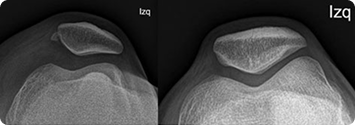

Son los amortiguadores fibroelásticos de la rodilla y tienen forma de media luna. El menisco medial se encuentra en la parte interna de la rodilla, y el menisco lateral está en el área externa. Cada menisco está inserto en la tibia y hace contacto con el fémur para cumplir el rol de amortiguador cuando ésta articulación está con carga.